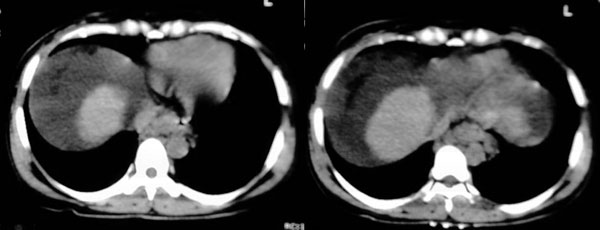

患者:女,43岁,自觉全身肿胀8个多月。b超提示:肝硬化、腹水,胆囊炎。胰、脾、肾未见明显异常。

肝脏体积变小,左右比例失调,右肝变小较剧,脾脏增厚,腹水征象明显考虑肝硬化、腹水

肝脏体积变小,左右比例失调,右肝变小较剧,脾脏增厚,腹水征象明显考虑肝硬化、脾大,腹水。病理性胆囊[胆囊小,比增厚]

肝脏体积缩小,左右肝比例失调,轮廓不规整,肝裂增宽,肝周见新月形液性密度影,脾脏增厚.应诊断为肝硬化,腹水,脾大.